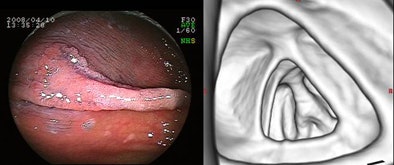

| Above, 23-mm adenoma (protruding lesion) in the rectum was seen at virtual colonoscopy (right). Below, 20-mm advanced adenoma (flat lesion) was detected only at conventional colonoscopy. All images courtesy of Dr. Kenichi Utano. |

| The overall detection rate was only 56%, based on the combined detection rate of 70% for LSTGs and 25% for LSTNGs. There was a significant difference in detectability of the two types by Fisher's exact test (p = 0.014). Interestingly, lesion size was not a significant factor in detectability. |